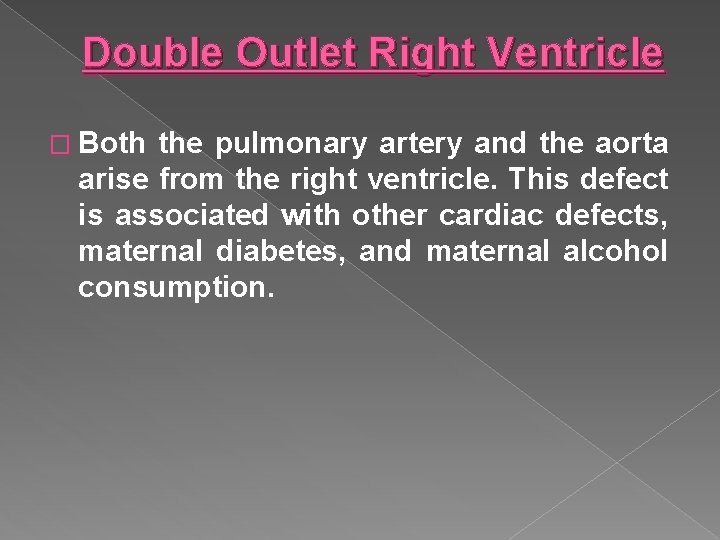

Double Outlet Right Ventricle � Both the pulmonary artery and the aorta arise from the right ventricle. This defect is associated with other cardiac defects, maternal diabetes, and maternal alcohol consumption.